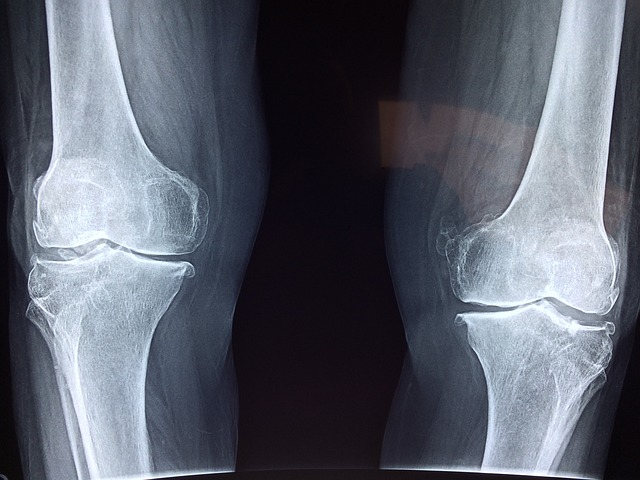

骨粗鬆症の原因は、 運動不足と

言っても過言ではありません。

こうして骨の密度が低くなり、

筋肉の量が減れば、

転倒しやすくなります。

骨の周りには必ず筋肉が

ついています。

その筋肉が力を出すと、

骨は物理的な刺激を受け、

骨の密度が高くなります。

逆に筋肉が力を出さないと、

骨の密度はどんどん

減って行ってしまいます。